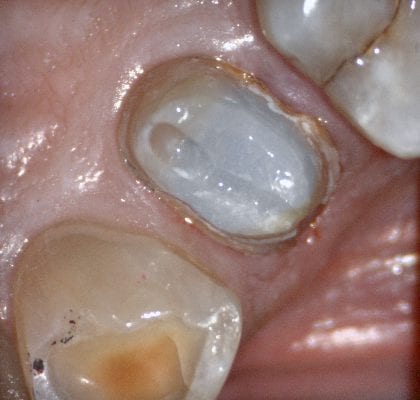

Case set up involved imaging the pre-existing condition in the pre-op catalog box. Excess information was cropped to reduce file size. The data was then copied to the maxillary arch catalog box and the area to prepared was edited out in preparation for final optical impressions.